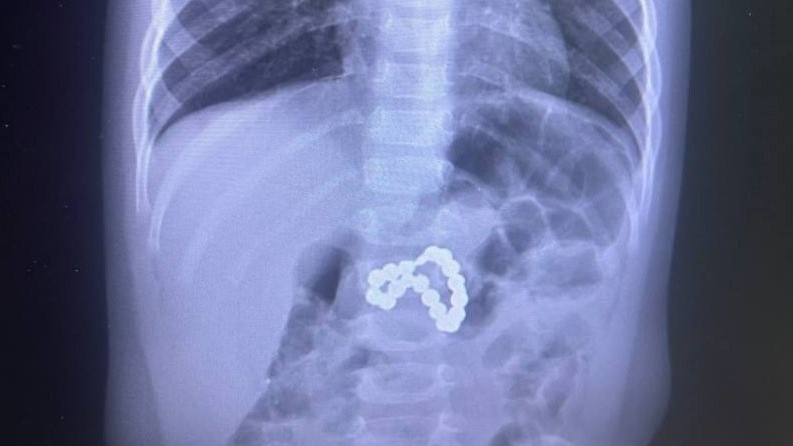

Врачи Сургутского центра охраны материнства и детства спасли ребёнка, который проглотил 13 магнитных шариков. Девочка младшего дошкольного возраста поступила к медикам с жалобами на боль в животе и рвоту. Во время обследования в желудке ребёнка обнаружили инородное тело. Предмет был похож на перекрученные бусы. Оказалось, что бусины - ни что иное, как круглые магниты. Случай уникален тем, что магнитов оказалось несколько. Часть из них осталась в желудке, вторая перешла с пищей в кишечник. Шарики примагнитились друг к другу, сцепив между собой органы девочки. В месте стыка, где соединились магниты, произошёл дефект кишечника и желудка. Четыре часа мультидисплинарная бригада врачей оперировала маленькую пациентку. К счастью, сейчас она уже идёт на поправку и проходит курс восстановительного лечения. Медики также рассказывают, что ежегодно в Сургуте они оперируют около 150 детей, проглотивших мелкие детали игрушек, магниты и батарейки. Ирина Кудринских, заместитель главврача по контролю к

Врачи Сургутского центра охраны материнства и детства спасли ребёнка, который проглотил 13 магнитных шариков.

Девочка младшего дошкольного возраста поступила к медикам с жалобами на боль в животе и рвоту. Во время обследования в желудке ребёнка обнаружили инородное тело. Предмет был похож на перекрученные бусы. Оказалось, что бусины - ни что иное, как круглые магниты.

Случай уникален тем, что магнитов оказалось несколько. Часть из них осталась в желудке, вторая перешла с пищей в кишечник. Шарики примагнитились друг к другу, сцепив между собой органы девочки. В месте стыка, где соединились магниты, произошёл дефект кишечника и желудка.